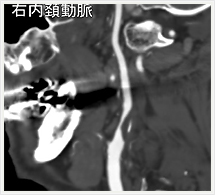

画像紹介(頭頚部血管編)

画像は、頚動脈の狭窄部分に“ステント”と呼ばれる金属性の網状の筒を留置して、血管を正常径まで拡張させる手術です。この治療は、内膜剥離術と比較して非侵襲的であり、高齢者やいろいろな合併症を持った方にも負担を少なくして行うことができます。術後の安静期間や入院期間も短いのが特徴です。